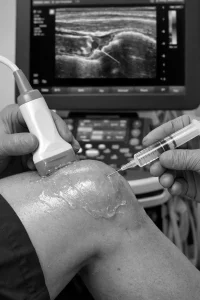

Os procedimentos minimamente invasivos incluem aplicações terapêuticas que atuam diretamente na fonte da dor.